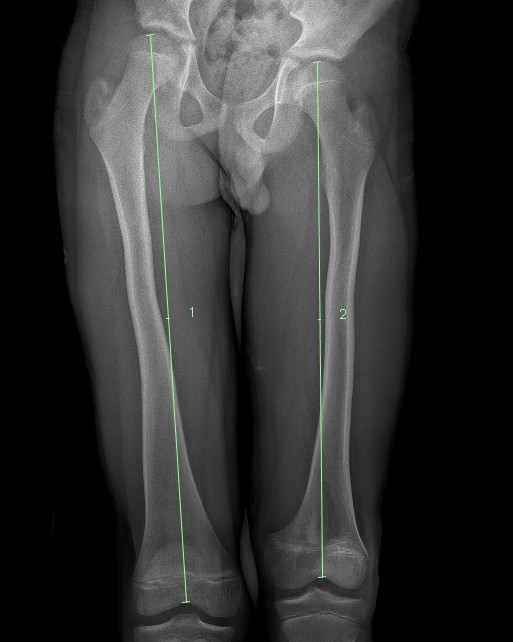

Complete growth arrest / Leg length discrepancy

SH1SH1LLD

Monitor 6 monthly

- plot short and long leg lengths on Mosely chart

- distal femur contributes 9 mm / year

LLDLLD

Manage LLD as per predicted difference

- contralateral femoral epiphysiodesis +/- femoral lengthening

www.boneschool.com/pediatrics/leg-length-discrepancy